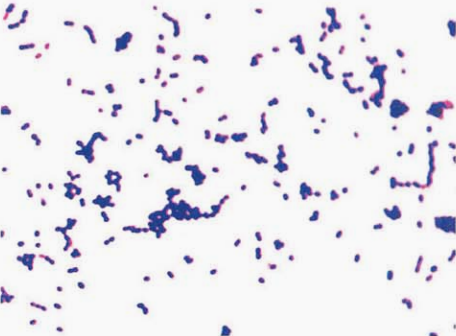

(一) 绿色气球菌形态与染色

革兰阳性球菌,直径1.0~2.0μm,多呈四联状或成簇排列,亦可单个、成对排列,液体培养更倾向于四联状排列(图 1)。

图 1绿色气球菌纯培养的镜下形态(革兰染色)